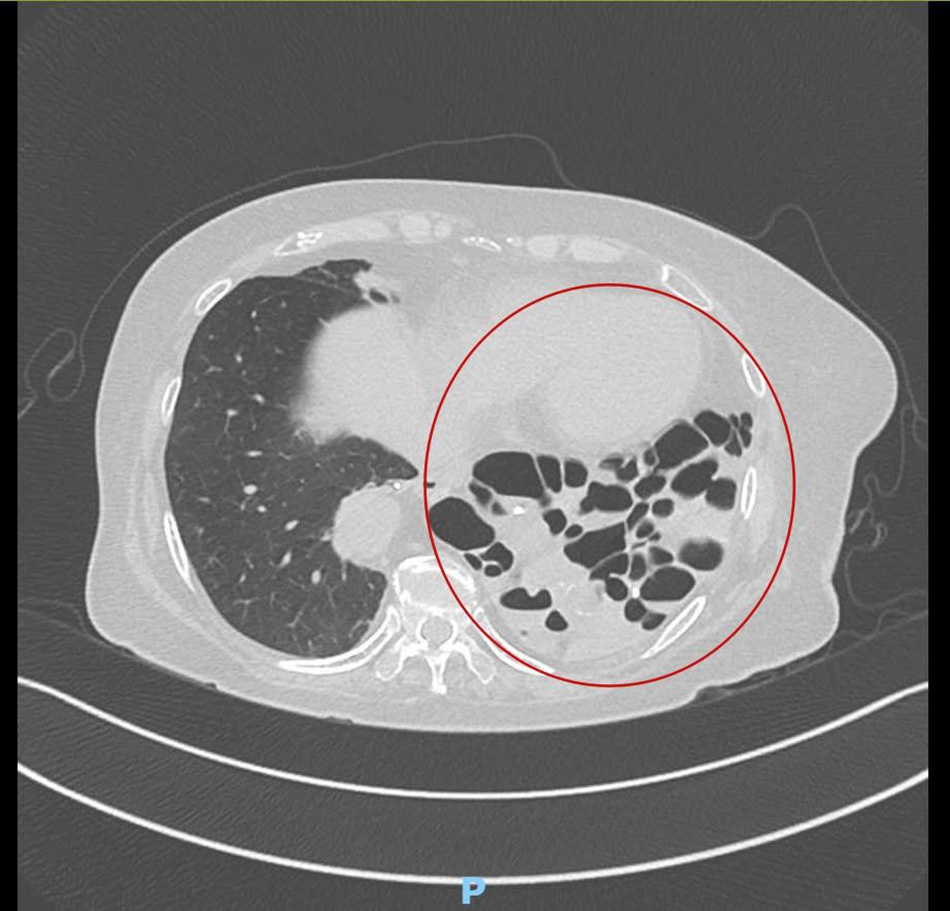

Phim chụp CT cho thấy phần phổi bên trái của bệnh nhân đã bị tổn thương nặng

“Khối tổn thương có kích thước khoảng 15-20cm, chiếm toàn bộ khoang phổi trái và chèn ép sang cả phổi phải. Bên trong chứa nhiều vi khuẩn nguy hiểm như E. coli, Pseudomonas. Đây là một ca giãn phế quản nặng và hiếm gặp: toàn bộ thùy phổi đã mất hoàn toàn chức năng, bị xơ hóa, chứa đầy dịch mủ và trở thành một ổ nhiễm trùng mạn tính”, bác sĩ Trung nhận định.